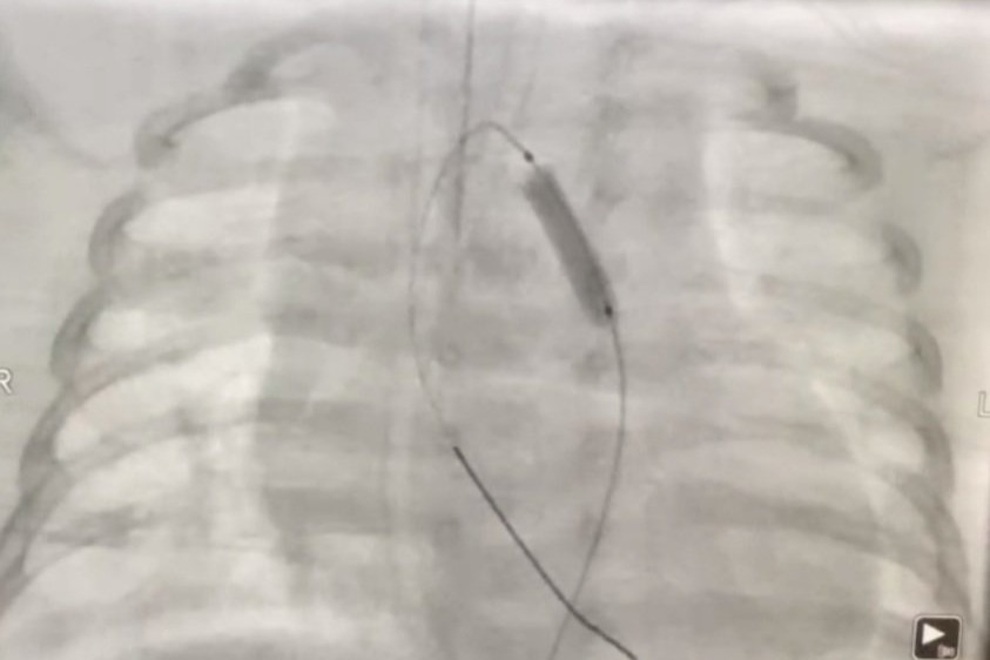

Quá trình các bác sĩ can thiệp nong eo động mạch cho bệnh nhi.

Được hội chẩn lãnh đạo, 21h cùng ngày, bệnh nhi được chuyển phòng can thiệp nong eo động mạch chủ cấp cứu. Sau một giờ can thiệp, xác định thủ thuật thành công, bệnh nhi ổn định, được bàn giao về khoa Hồi sức tích cực sơ sinh. Hiện bệnh nhi ổn định, tự thở, môi hồng, không còn khó thở, ăn bú tốt.